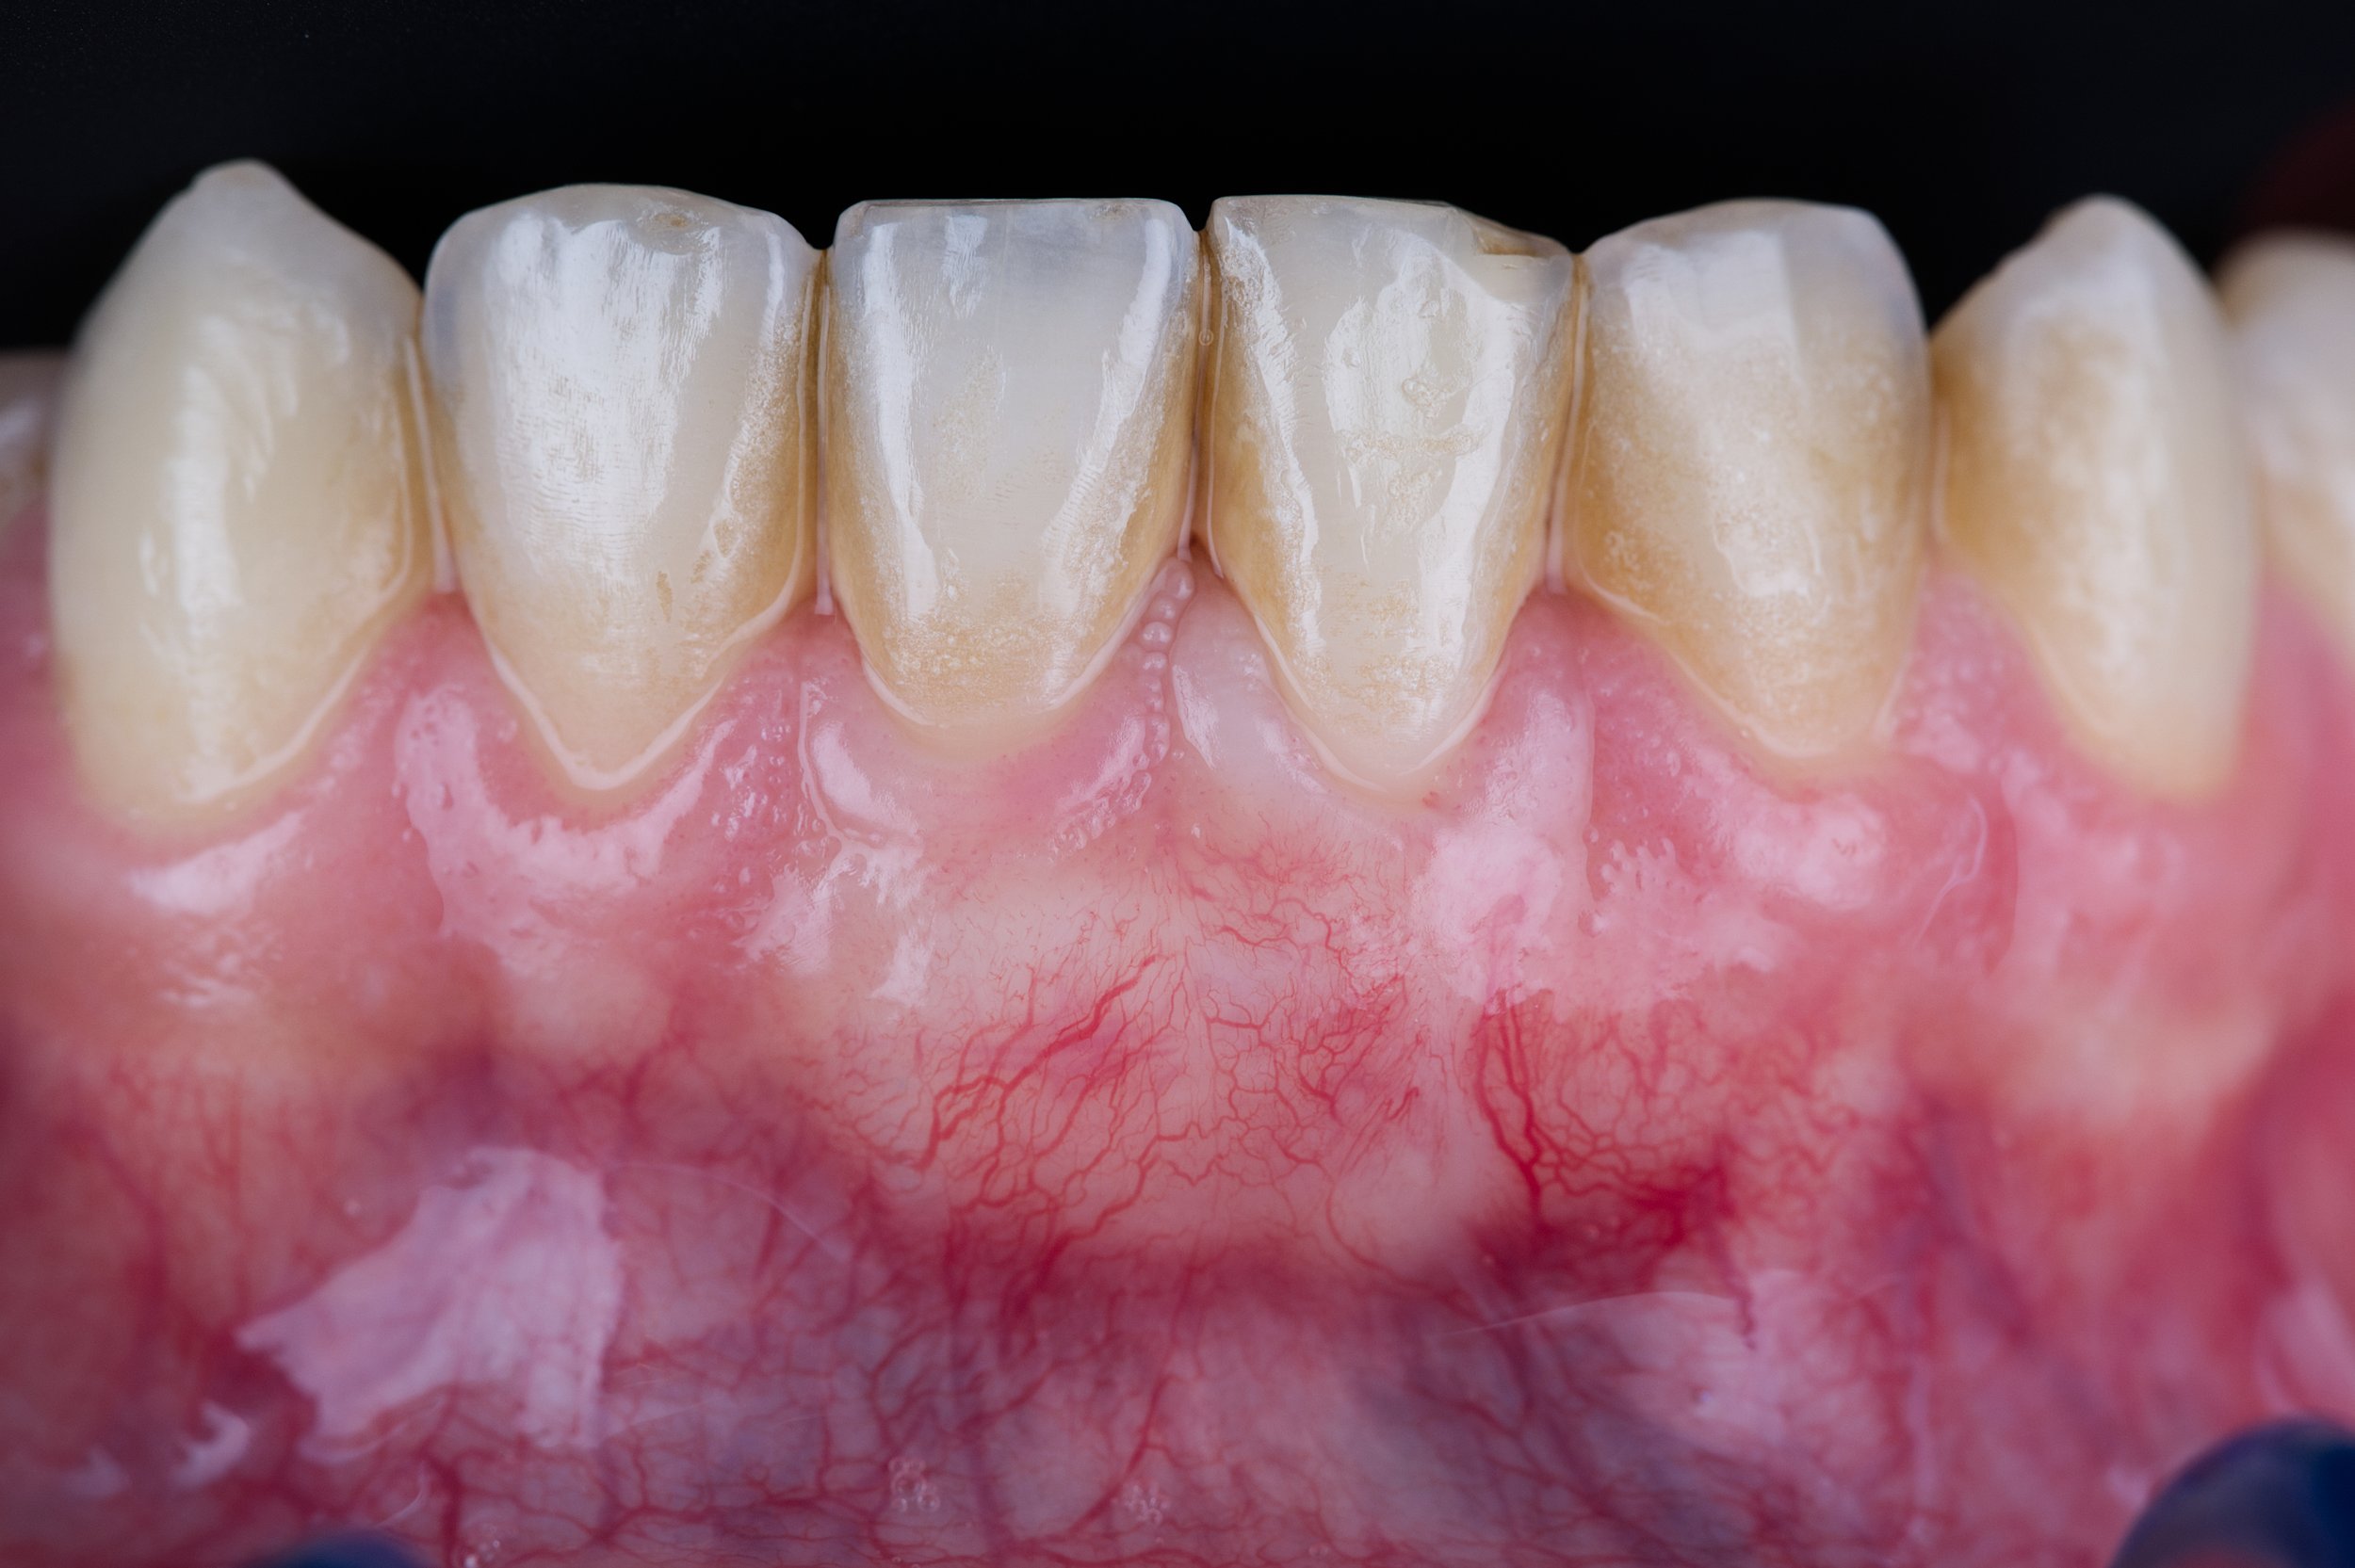

Après 3 mois de cicatrisation, la gencive est mature, le recouvrement est complet, et Pierre sera suivi tous les ans pour que les résultats restent stables dans le temps.